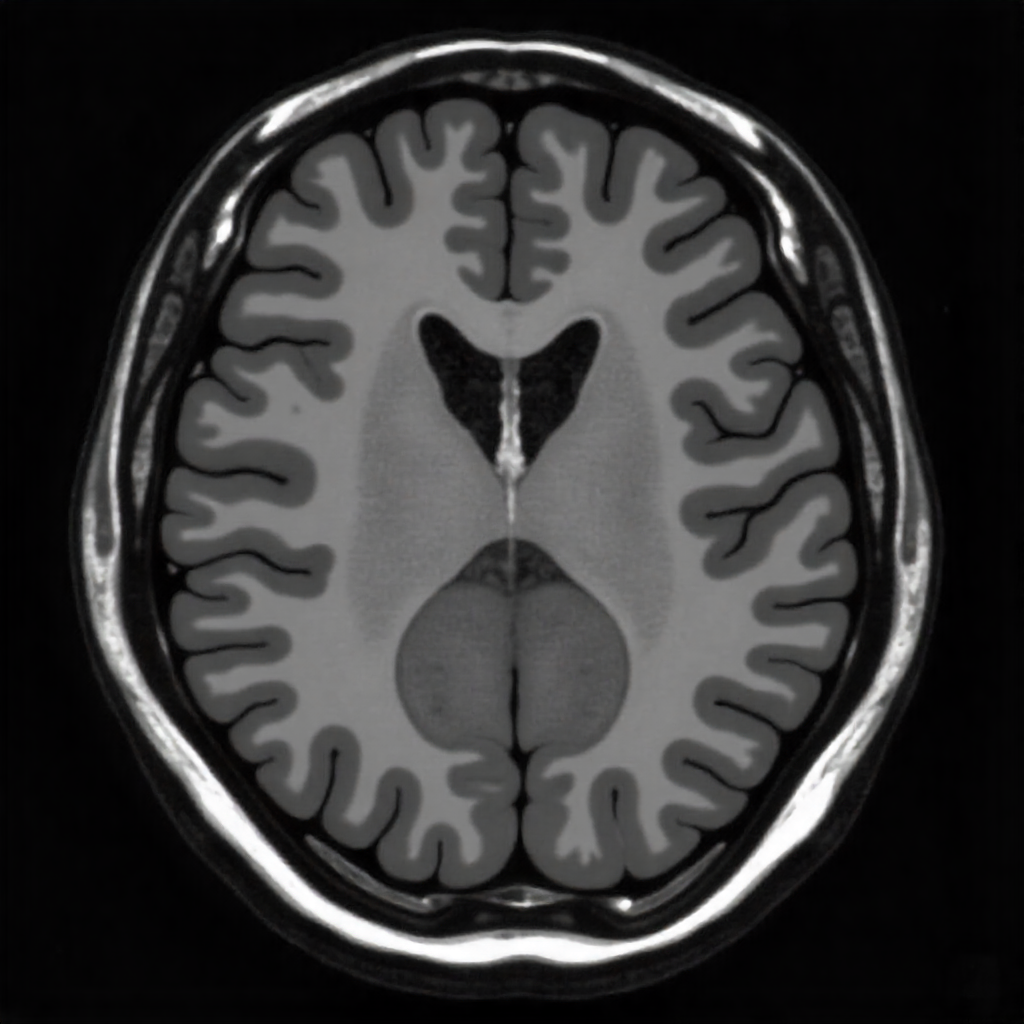

Proje, beyin taramalarını hızlıca yorumlayıp uzmanlara ilk bakışta rehberlik edecek sade öngörüler sunmayı amaçlar. Sistem, kritik alanları işaretleyerek doktorların dikkatini en önemli bölgelere yönlendirir.

Beyin MRI Tarama Görseli